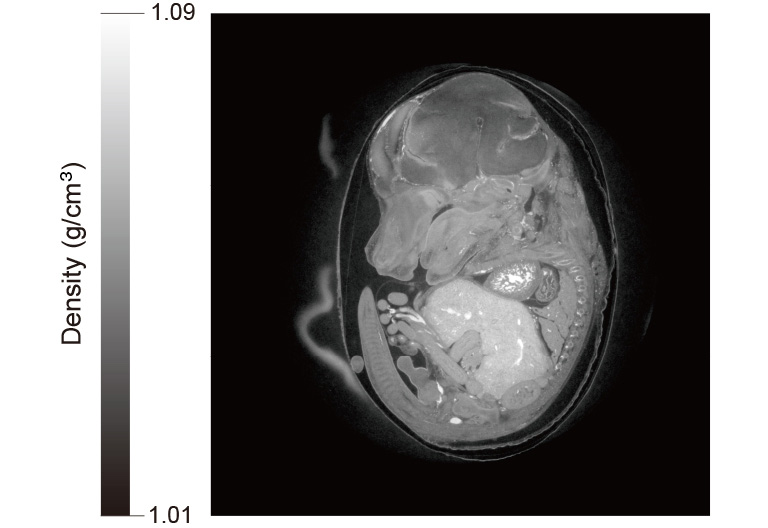

The second point is the acquisition speed. In general, increasing the frame rate of a camera reduces the number of photons per frame, resulting in a decrease in S/N. However, the ORCA-Quest not only has a high frame rate of 120 frames per second but also has high quantum efficiency and very low readout noise. As a result, it has the advantage of reducing the measurement time in X-ray micro-CT experiments and live imaging of biological specimens. In our recent experiments, we performed high-speed live imaging of the lungs of small animals.

Camera: ORCA-Quest qCMOS camera C15550-20UP

Optics: High-resolution X-ray imaging system (M11427)

Beam line: SPring-8 BL20B2

Exposure time: 15 msec

Total measurement time: 6.5 min

Data courtesy of: SPring-8 BL20B2 beamline by Dr. Masato Hoshino, Senior Scientist in Japan Synchrotron Radiation Research Institute (JASRI)